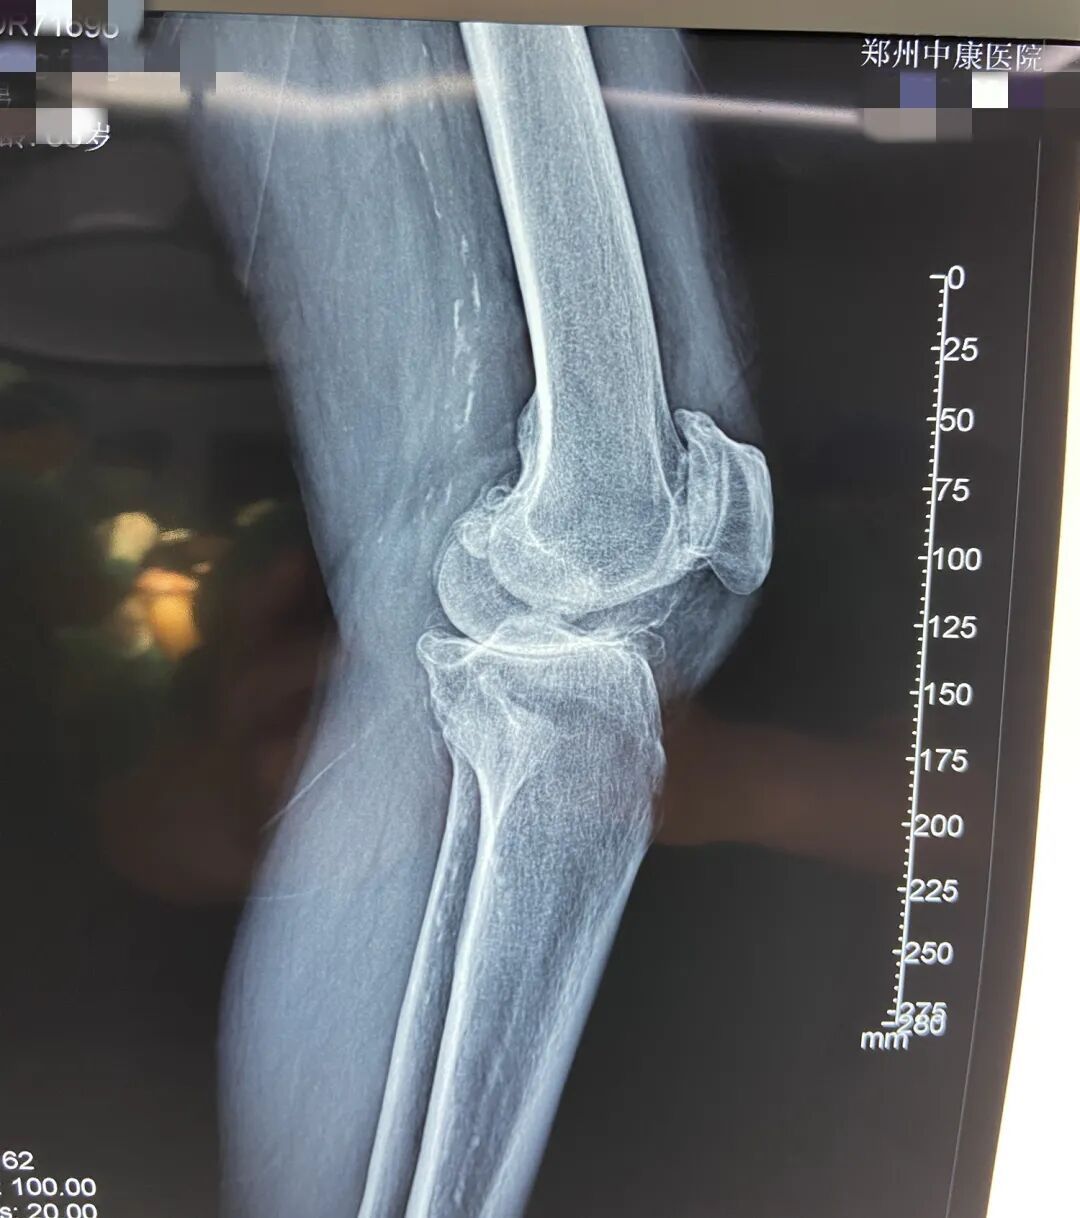

同样受益的还有家住苟堂镇的梁某,6月1日在中康医院进行了膝关节置换手术,医保报销后个人支付费用大大降低。